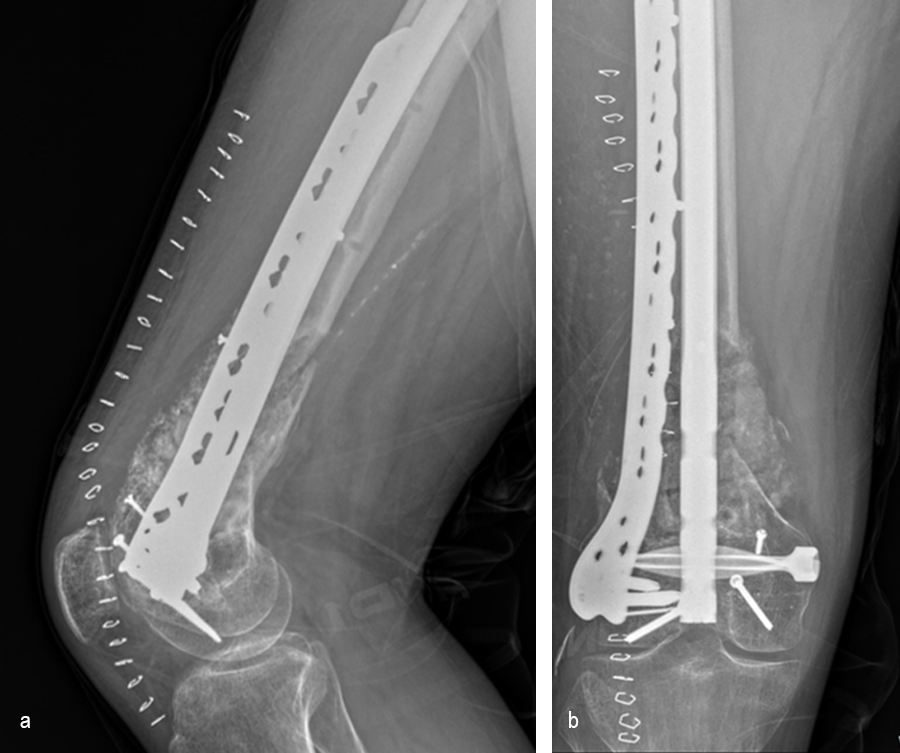

At the 3-week follow-up (post-graft cage, Fig 12), the patient’s wounds were healthy. He had a range of motion (ROM) of 0–80 in his right knee. He was allowed weight bearing as tolerated (WBAT) with crutches.

At the 3-month follow-up (Fig 13), the patient had a ROM of 0–120 in his right knee. His quadricep muscles had significantly recovered and he was able to WBAT with support from a cane.

At the 6-month follow-up (Fig 14), the patient was able to WBAT on the right lower extremity. He had some ankle pain and a ROM of 0–125 in his right knee. The patient was able to walk without any assistance device.